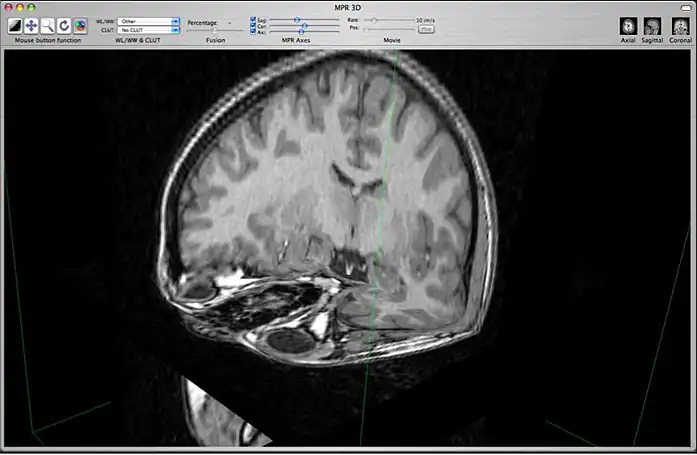

c) 3D Orthogonal MPR

3D orthogonal MPR mode

This mode allows you to display a 3D representation of the volume with 3D orthogonal MPR slices. You can change the position of the orthogonal slices by using the 3 sliders located in the toolbar:

Positions of orthogonal slices

Hide or show slices by clicking in the check boxes.